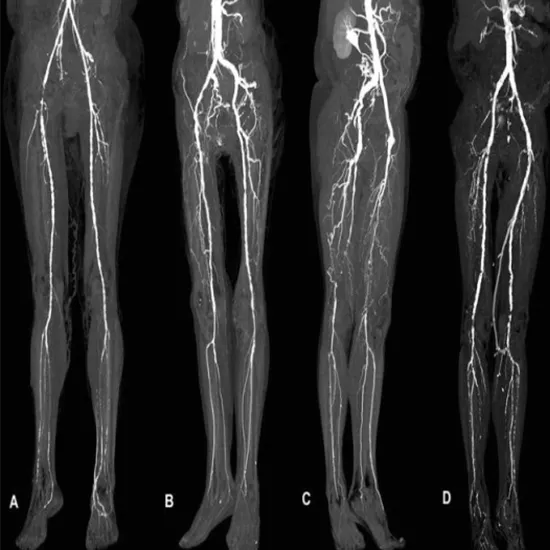

Peripheral angiography is a test that examines and finds blocked or narrowed blood vessels or arteries carrying blood to the brain, arms, and legs using X-rays and a special dye.It is very helpful for doctors to find the narrowed or blocked areas in the peripheral arteries.

Peripheral angiography assists doctors in identifying blocked or narrowed arteries that carry blood to the legs, limbs, knees, ankles, and arms. The doctor who uses.

Doctor asks for CT Peripheral Angio to diagnose bleeding, inflammation, and swelling of blood vessels. The symptoms you may experience are